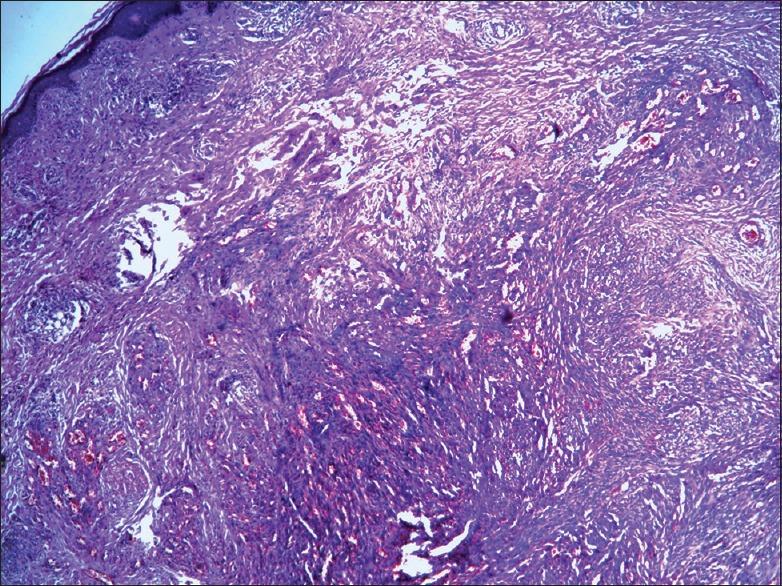

Castleman's disease (CD) or giant lymph node hyperplasia is a rare disorder that can be unicentric or multicentric. Multicentric Castleman's disease (MCD) is manifested by generalized lymphadenopathy, hepatosplenomegaly, polyclonal hypergammaglobulinemia, hematological abnormality, and constitutional symptoms. Human herpesvirus 8 (HHV-8) infection is present in nearly 100% MCD associated with HIV-1 infection, but in about 50% of cases of HIV negative. Herein, we report a 77-year-old man with systemic involvement and skin lesions on the anterior aspect of both legs in the previous site of saphenous vein angioplasty. Co-existence of MCD with Kaposi's sarcoma (KS) led us to present this rare case.

卡斯尔曼病(CD)或巨大淋巴结增生是一种罕见的疾病,可分为单中心型或多中心型。多中心卡斯尔曼病(MCD)表现为全身淋巴结肿大、肝脾肿大、多克隆高球蛋白血症、血液学异常和全身症状。在与HIV-1感染相关的MCD中,几乎100%存在人类疱疹病毒8(HHV-8)感染,但在约50%的HIV阴性病例中也有该病毒感染。在此,我们报告一名77岁男性,有全身受累情况,且双腿前侧在之前大隐静脉血管成形术部位出现皮肤病变。MCD与卡波西肉瘤(KS)共存促使我们呈现这一罕见病例。